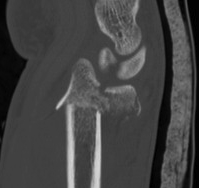

Distal Radius Fracture Articular Step Coronal CTDistal Radius Fracture Articular Step Sagittal CT

Articular incongruency > 2 mm

Distal Radius Fracture DRUJ incongruentDRUJ FractureDRUJ Fracture CT

Sigmoid notch disruption and DRUJ instability